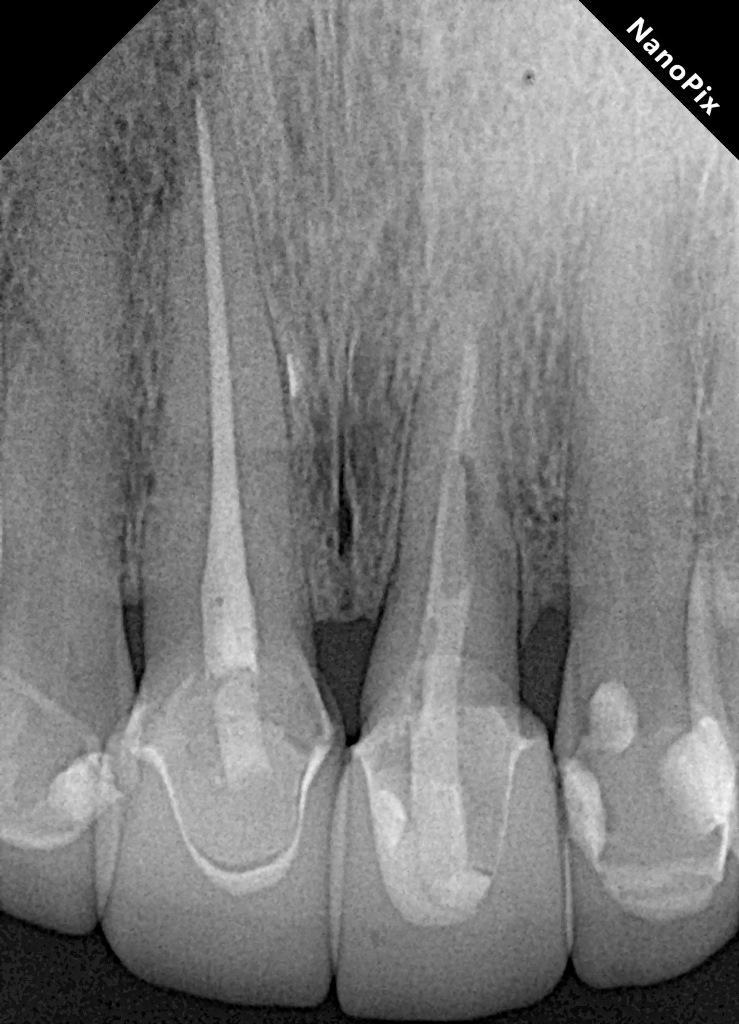

Рентгенологическое исследование, проведенное через два года после экструзии, выявило хорошее периапикальное заживление и продолжающийся вертикальный рост кости на межзубном гребне, главным образом в дистальной области (фото 5). Сообщалось, что нормальный контур периодонтальной связки может наблюдаться через три месяца после операции, а периапикальное восстановление и восстановление рентгенопрозрачности обычно наблюдаются через шесть месяцев, а также минимальная потеря костной массы, часто связанная с повреждением кости в процессе экструзии. Через два года наблюдалось полное восстановление периапикальной ткани и продолжающееся ремоделирование кости, главным образом в области дистального гребня (фото 6). Зуб остается бессимптомным, немобильным и полностью функциональным с эстетической и биологической точек зрения (фото 7). Рентгенологическая картина после четырехлетнего периода наблюдения показала стабильные результаты (фото 8).

Фото 8: После четырехлетнего наблюдения периапикальная рентгенограмма показала отсутствие признаков воспаления в периапикальной области, отсутствие признаков резорбции корня, увеличение костной массы в области дистального гребня и нормальное состояние периодонтальной связки.